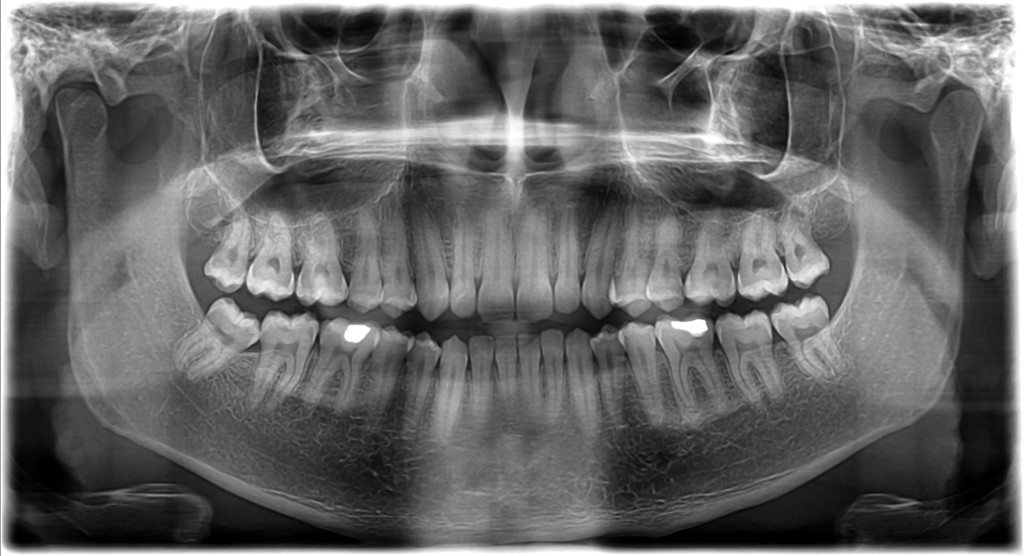

- Velký rentgenový snímek ortopantomogram zobrazí všechny zuby, obě čelisti, čelistní dutiny i čelistní klouby.